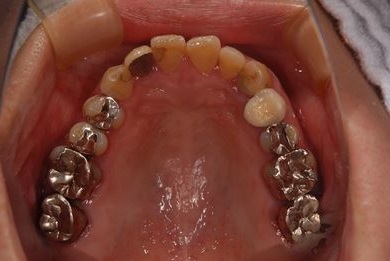

| 性別/年齢 | 女性 / 51歳 | ||||||||||||||||||||||||||||||||

| 主訴 | 前の歯の治療後の変色が気になる。詰め物がとれた箇所あり。痛みあり。 | ||||||||||||||||||||||||||||||||

| 治療方針 | セラミック治療にて、審美的回復を行う。 | ||||||||||||||||||||||||||||||||

| 治療内容 | オールセラミッククラウン7本(オールセラミック用土台1本)、ハイブリッドセラミッククラウン10本(ハイブリッドセラミック用土台9本)、ハイブリッドセラミックインレー1本 | ||||||||||||||||||||||||||||||||

| 総治療費 | 961,800円 | ||||||||||||||||||||||||||||||||

| 治療期間 | 10ヶ月 |